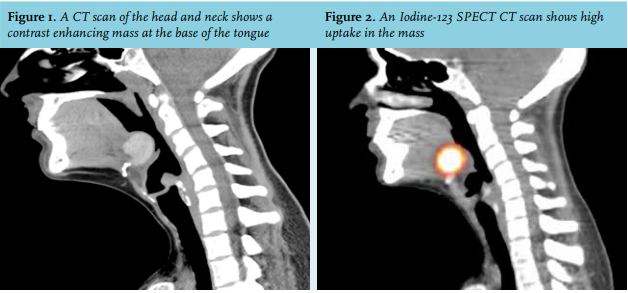

A 30-year-old Caucasian woman was referred to the ear-nose-throat outpatient clinic complaining of dysphagia, otalgia and fever for four days. She did not have any relevant medical history. Under the suspicion of a pharyngeal abscess, a computed tomography (CT) scan was made, confirming the diagnosis; however, a contrastenhancing mass at the base of the tongue was also visible (figure 1). An iodine-123 single photo emission tomography (SPECT)/CT scan was made, showing high iodine uptake in the lesion at the base of the tongue (figure 2).